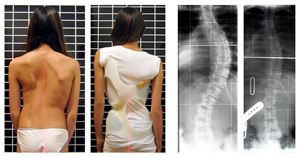

特發(fā)性脊柱側(cè)彎

特發(fā)性脊柱側(cè)凸是脊柱的側(cè)偏畸形,原因不明。因?yàn)檫€有脊椎旋轉(zhuǎn)而不僅僅是偏離,所以術(shù)語脊柱側(cè)彎也被用來描述畸形。

青少年特發(fā)性脊柱側(cè)彎的特征是脊柱三維畸形伴有側(cè)彎加椎體旋轉(zhuǎn)。

身體檢查涉及姿勢和身體輪廓的基線評估。

注意雙肩是否不平,是否有肩胛骨突出。

當(dāng)后肋骨在曲線的凸側(cè)向后推動(dòng)時(shí),可能會(huì)出現(xiàn)肋骨隆起。

此外,肋在凹側(cè)緊密靠近,在凸側(cè)分開。